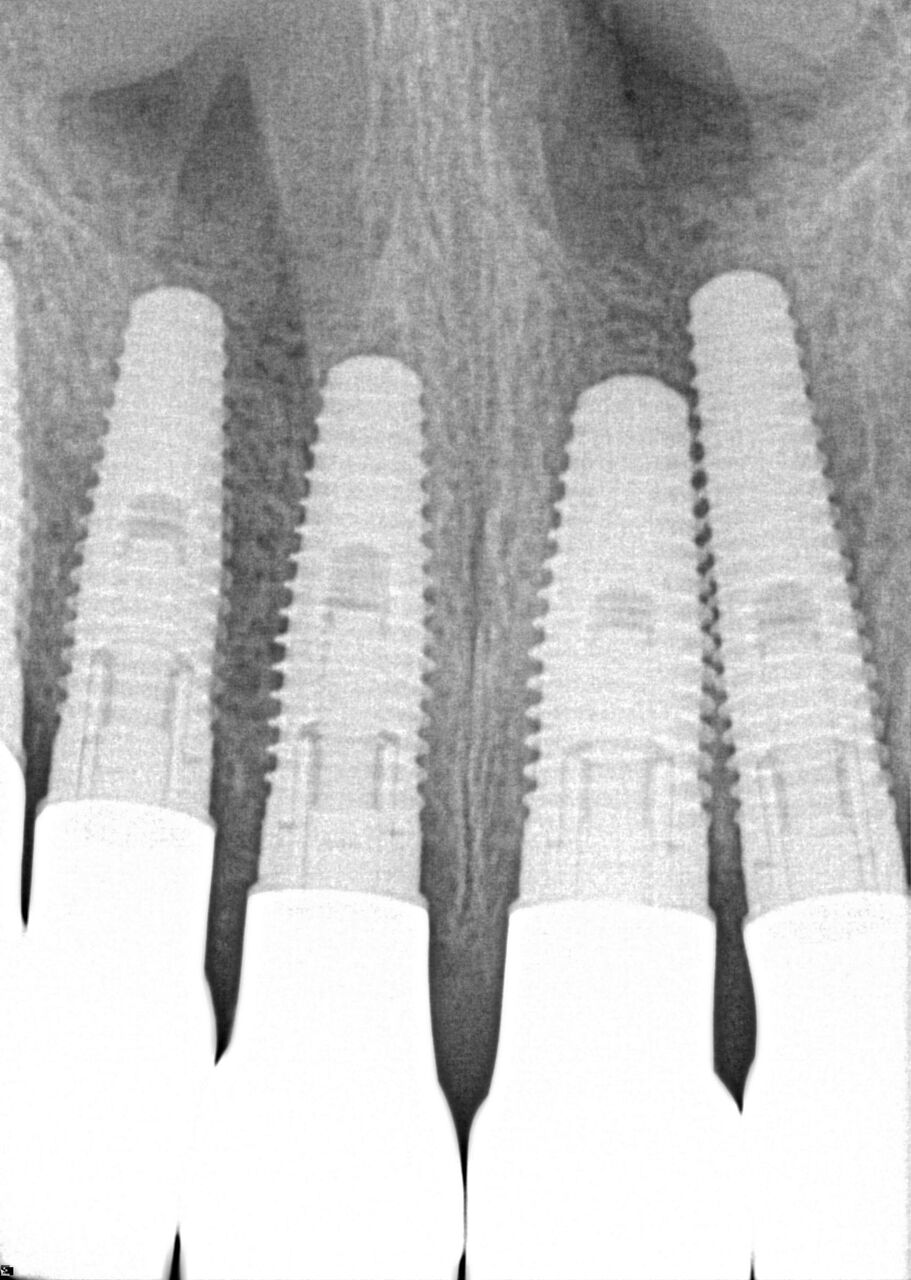

(17.) Case 3 initial radiograph of bridge on Nos. 6 through 9 and crown on No. 10.

Figure 17

(18.) Case 3 initial radiograph of bridge on Nos. 6 through 9 and crown on No. 10.

Figure 18

(20.) 6-month integration confirmation of Nos. 6 through 10.

Figure 20

(21.) 6-month integration confirmation of Nos. 6 through 10.

Figure 21

(24.) Radiograph of postoperative individual crowns on Nos. 6 through 10.

Figure 24

(25.) Radiograph of postoperative individual crowns on Nos. 6 through 10.

Figure 25

A 42-year-old man presented with a very loose bridge on Nos. 6 through 9 with periodontally compromised retainers on Nos. 6 and 9 (Figure 17 through Figure 19), and endodontically involved No. 10 with a calcified canal. Teeth Nos. 6, 9, and 10 were extracted, the sockets fully debrided, and pontic soft tissue on Nos. 7 and 8 sculpted to be symmetrical in soft tissue contour with the contralateral lateral incisor and central incisor locations. Implants were secured in position Nos. 6 through 10 (Figure 20) in excess of 45 Ncm, the bone was milled to provide unimpeded seating of temporary abutments, and temporary crowns were fabricated chairside and adjusted to be out of occlusion in centric relation and all excursions. The temporary crowns were cemented after extrusion of excess cement extraorally and the patient was prescribed antibiotics, analgesics, and instructed in postoperative care particular to immediately provisionally restored implants. At 6 months, integration was confirmed (Figure 20 through Figure 23) and after placement of scanning abutments, the implants and soft tissues were scanned. Final crowns were fabricated from the scanned images and were cemented after extrusion of excess cement extraorally (Figure 24 through Figure 26), and oral hygiene procedures were reviewed.